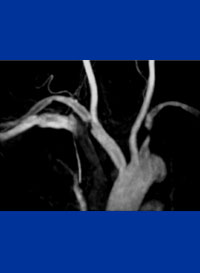

症例6

67歳 男性

検診異常

平成15年より腹部大動脈瘤を指摘。

平成18年1月CTにてφ5cm大のAAAを認め7月当院紹介受診。

56歳 AMI→PCI

64歳 Rectal Ca→ope

高血圧(+) 糖尿病(−) 喫煙歴(15本×30年)

Cook Zenith AAA stent graft